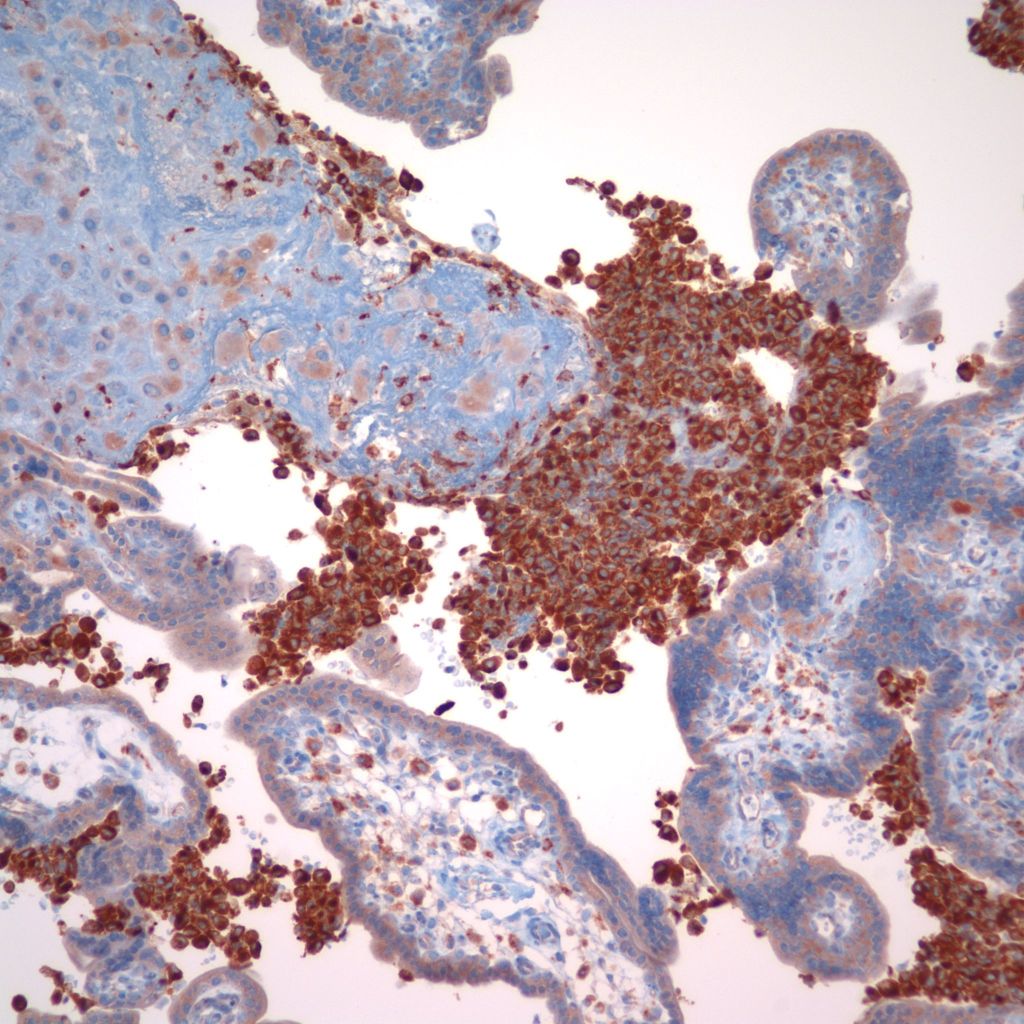

CD68 or alkaline phosphatase: to confirm that the intervillous cells are monocytes, but is not required for meeting the diagnostic criteria

C4d: to show evidence of complement fixation on the microvillous surface of the syncytiotrophoblast. While further study is needed, the subclassification of intervillous monocyte accumulations into those with and without complement fixation and the subclassification of villitis of unknown aetiology with intervillous monocytes into those with and without complement fixation may prove to be a useful distinction.

C4d: One study of CHIV compared 3 histologic groups of placentas demonstrating intervillous histiocytes: Few intervillous monocytes, massive intervillous monocytes, and intervillous monocytes associated with villitis of unknown aetiology18. Each group was further divided into subcategories based on the extent of c4d immunostaining of the microvillous surface of the syncytiotrophoblast. The outcome variables were fetal death or growth restriction. In the analysis, without a formal ROC study, it appeared that staining less than 25% of the villous surface was a natural cut off point from greater than 25%. As can be seen in the Table 1 of the raw data, that with rare exceptions, all the cases with less than 25% of c4d trophoblast staining, and often without any staining, were either associated with few intervillous monocytes, or with villitis. Fetal death or growth restriction was almost always associated with more than 25% of the villous surface stained with c4d. The lack of statistical significance in the comparisons is likely due to small sample size.

1. Direct evidence of Immune injury in intervillositis: The accumulation of monocytes in the intervillous space is the dominate evidence of an immune origin of intervillositis. The accumulation is likely due to both a chemotactic response and increase in either a cell adhesion molecular on the monocyte surfaces or possibly a secondary ligand that is linking monocyte surface molecules. One piece of evidence of an immunologic injury is the staining of the microvillous surface of syncytiotrophoblast by c4d, a stable complement product used routinely in pathology laboratories in identify antibody-mediated rejection in biopsies of transplanted organs. T-cells have been identified as a minority population in intervillostitis, but a regulatory role cannot be excluded. There is evidence in one study of in vitro T-cell activation.